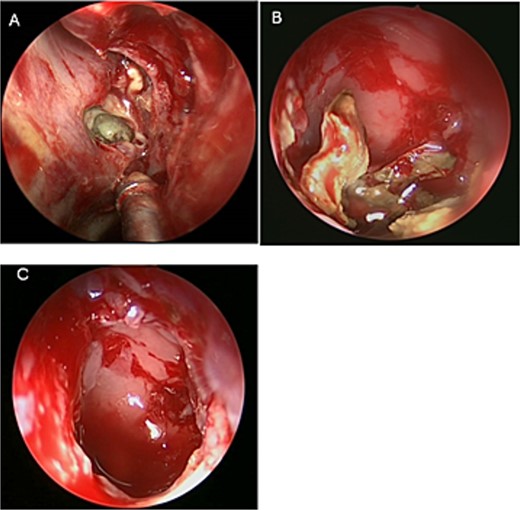

A 36 years-old man with no previous history of medical disease presented to the otolaryngology clinic with a chief complaint of headache that was associated with pressure feeling mainly in the occipital area. He also reported a post-nasal drip. The patient underwent a non-contrast paranasal sinus CT scan (Fig. 1) that demonstrated an isolated sphenoid sinus homogenous opacification, most likely representing sphenoid fungal ball. A decision was made to proceed with endoscopic sphenoidotomy (Fig. 2) to clean and remove the debris, which confirmed the diagnosis of sphenoid sinus fungal ball.

Intra-operative (A and B) endoscopic sphenoidotomy showing fungal debris, with post-operative examination (C) showing clean wide sphenoid sinus free from fungal debris.